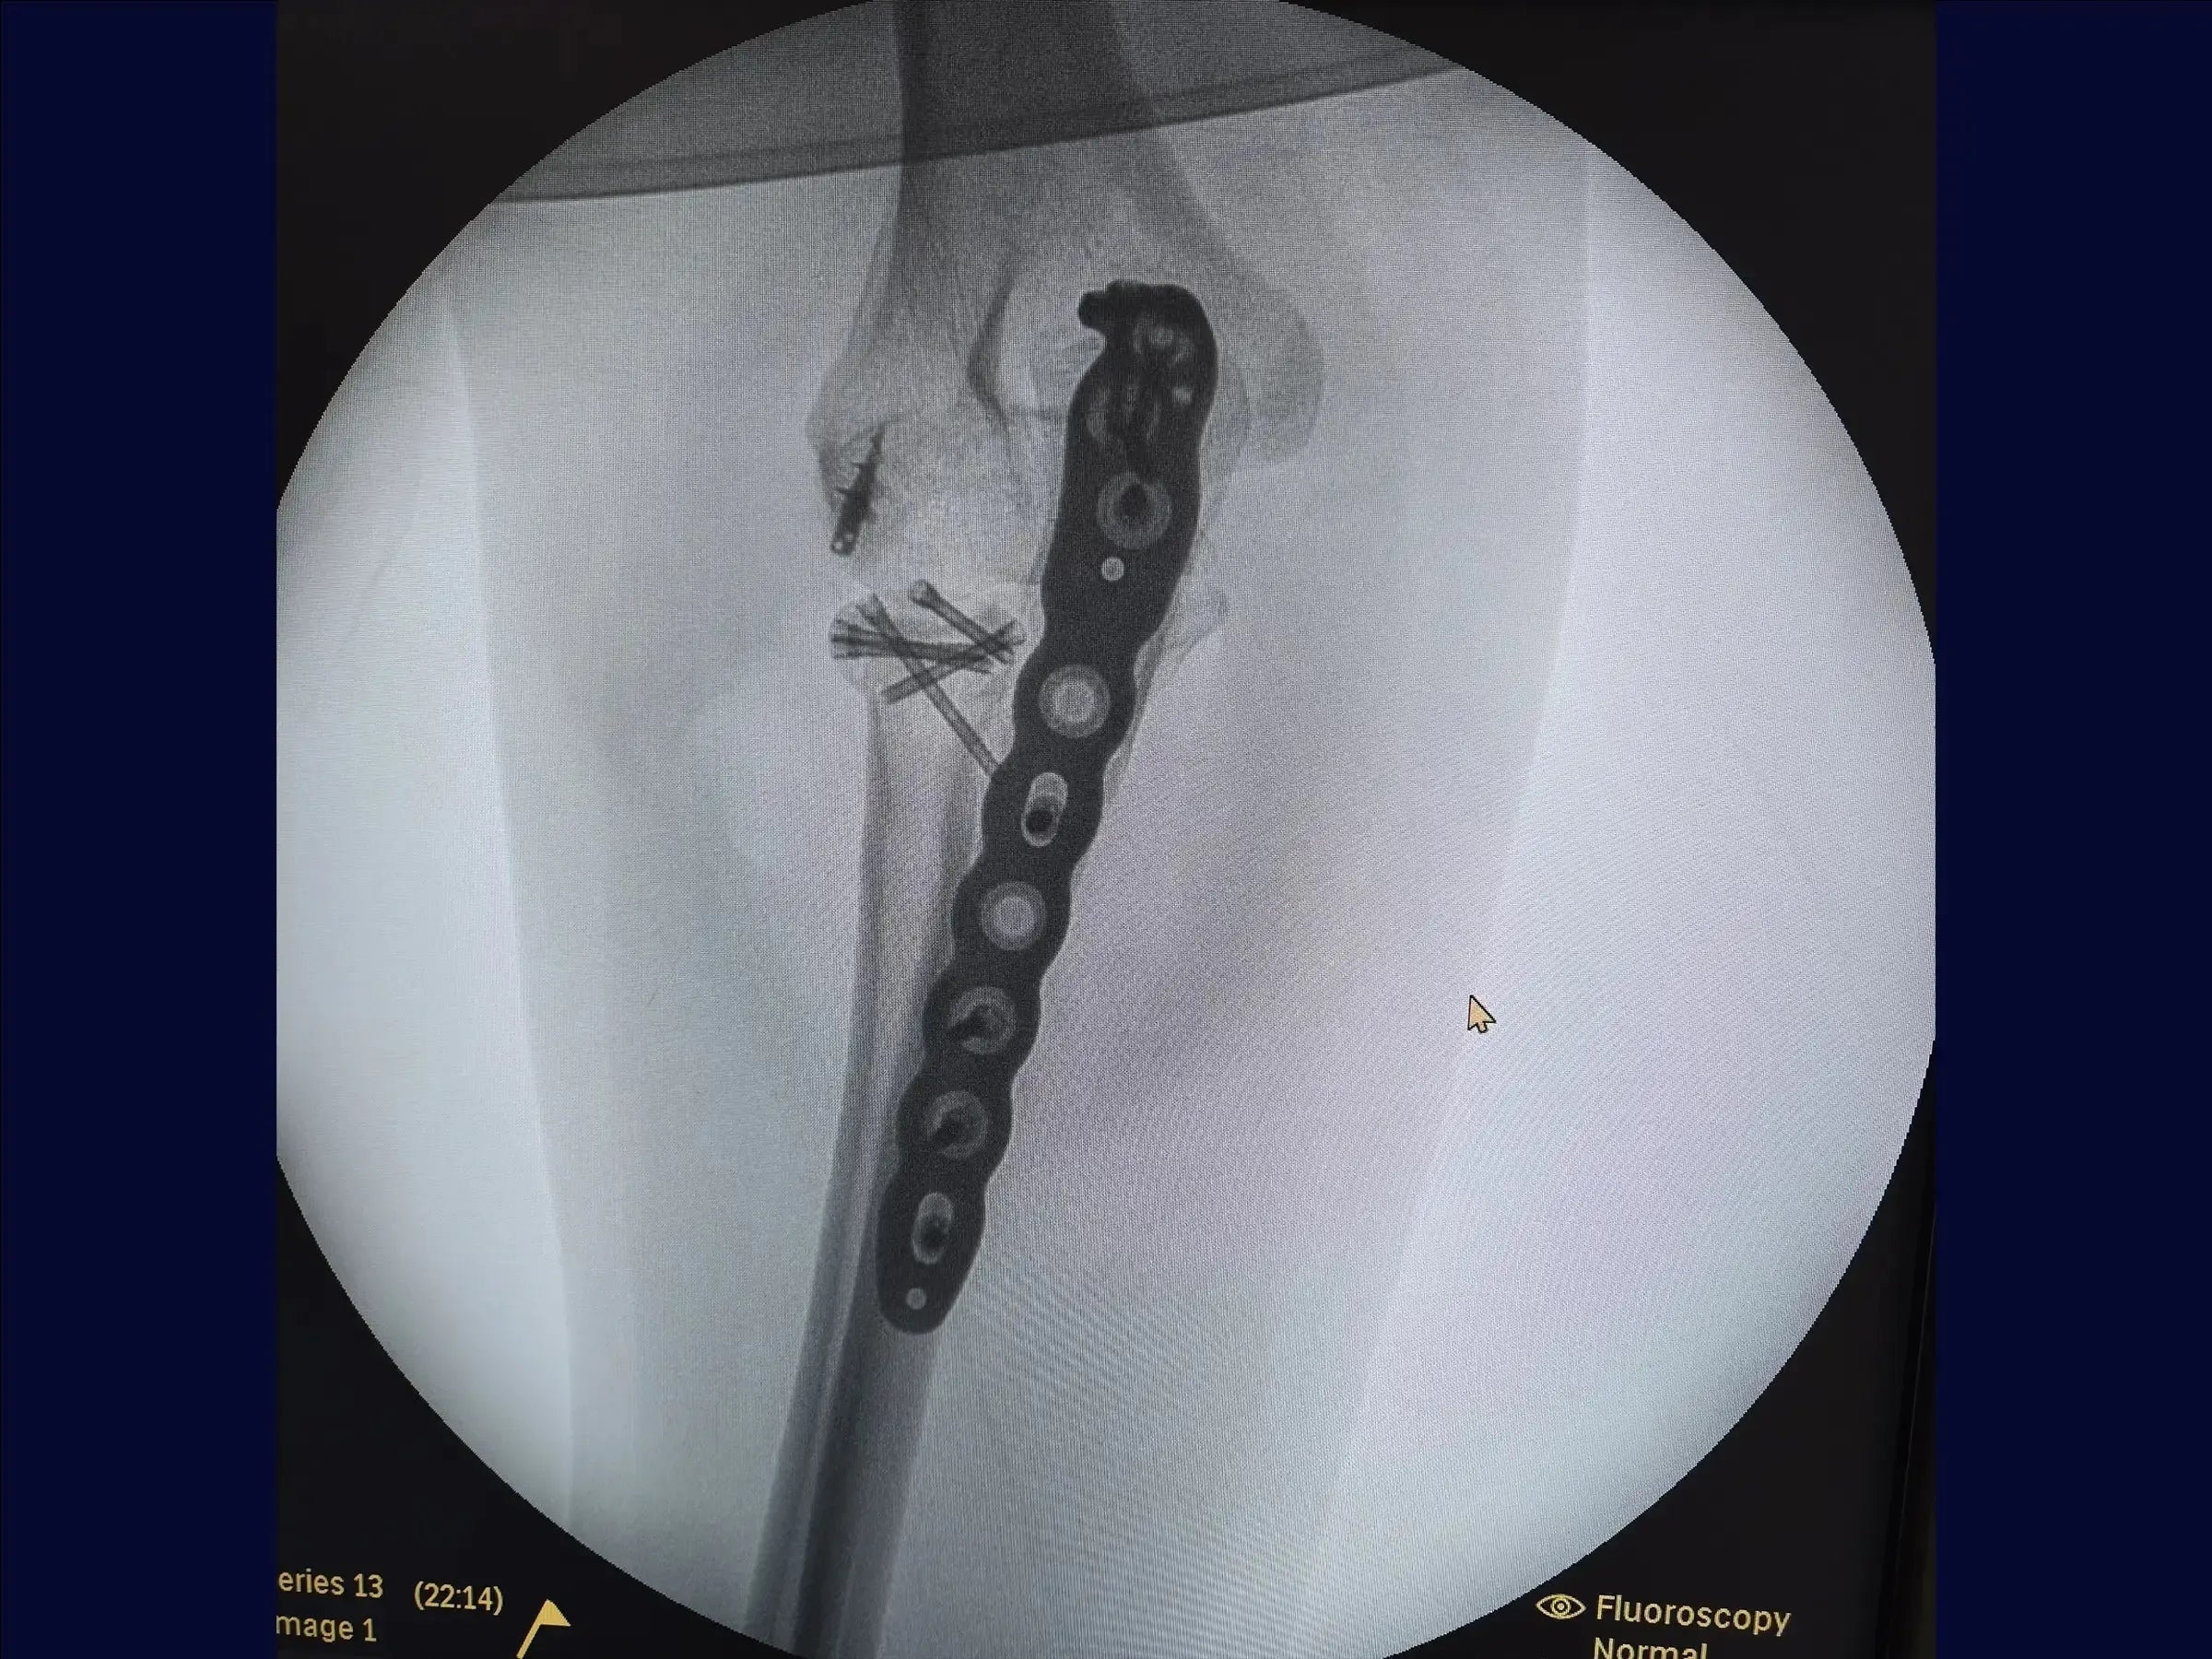

- Fijación estable con placas y tornillos.

- Fijación del cúbito : reducción anatómica del componente metafisario y preparación del lecho para la colocación de la placa con mínima lesión muscular.

- Placas y cierre: Fijación progresiva con tornillos dinámicos y bloqueados. Cierre anatómico de la fascia y la aponeurosis, guiado mediante marcas cutáneas.

- Postoperatorio : Movilidad inmediata con liberación de la flexión y pronación/supinación. Extensión limitada a 45° durante las primeras semanas para preservar la estabilidad.